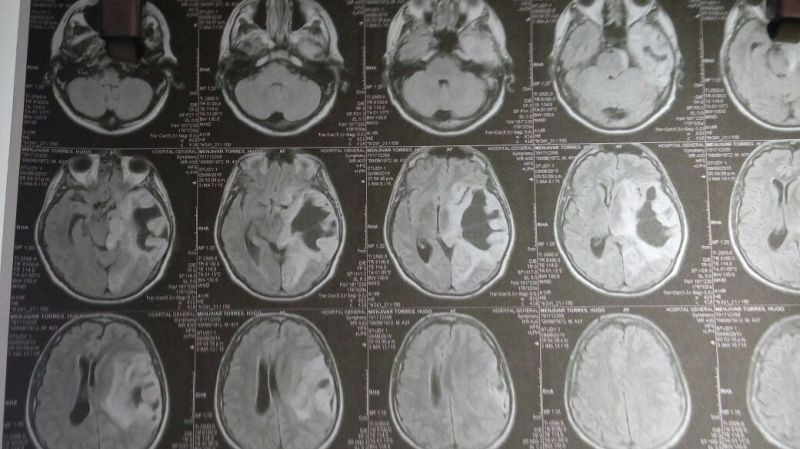

Oligodendroglioma temporal izquierdo Imagenes MRI Preoperatorio

Oligodendroglioma temporal Imagenes MRI Preoperatorio